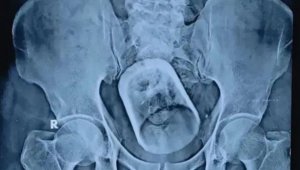

- 印度男子腹痛,肚里惊现整个茶杯!医生:细思极恐(图)